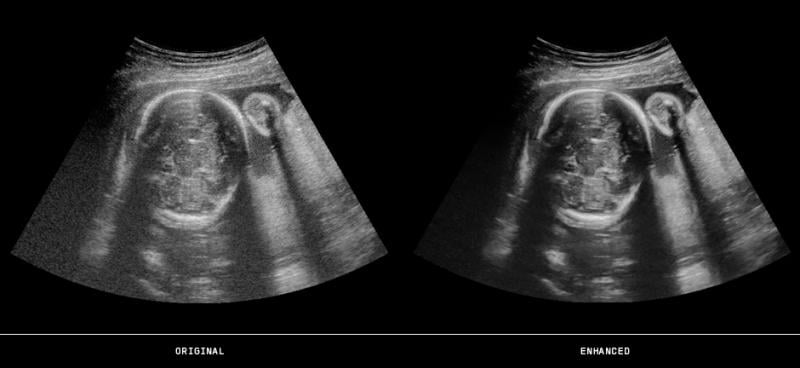

3D-4D ultrasound of a fetus imaged with a GE Volusion E10 system. It shows the yoke sac.